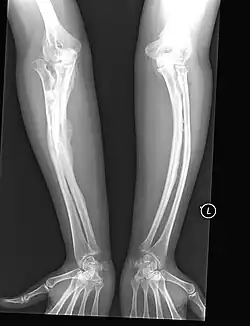

The main symptom of osteogenesis imperfecta is fragile, low mineral density bones; all types of OI have some bone involvement.[5] In moderate and especially severe OI, the long bones may be bowed, sometimes extremely so.[28] The weakness of the bones causes them to fracture easily—a study at the Endocrine Unit at the National Institute of Child Health in Karachi, Pakistan found an average of 5.8 fractures per year in untreated children.[29] Fractures typically occur much less after puberty, but begin to increase again in women after menopause and in men between the ages of 60 and 80.[1]: 486

Diagnosis is typically based on medical imaging, including plain X-rays, and symptoms. In severe OI, signs on medical imaging include abnormalities in all extremities and the spine.[97] As X-rays are often insensitive to the comparatively smaller bone density loss associated with type I OI, DEXA scans may be needed.[5]: 1514

An OI diagnosis can be confirmed through DNA or collagen protein analysis, but in many cases, the occurrence of bone fractures with little trauma and the presence of other clinical features such as blue sclerae are sufficient for a diagnosis. A skin biopsy can be performed to determine the structure and quantity of type I collagen. While DNA testing can confirm the diagnosis, it cannot absolutely exclude it because not all mutations causing OI are yet known and/or tested for.[83]: 491–492 OI type II is often diagnosed by ultrasound during pregnancy, where already multiple fractures and other characteristic features may be visible. Relative to control, OI cortical bone shows increased porosity, canal diameter, and connectivity in micro-computed tomography.[98] OI can also be detected before birth by using an in vitro genetic testing technique such as amniocentesis.[99]